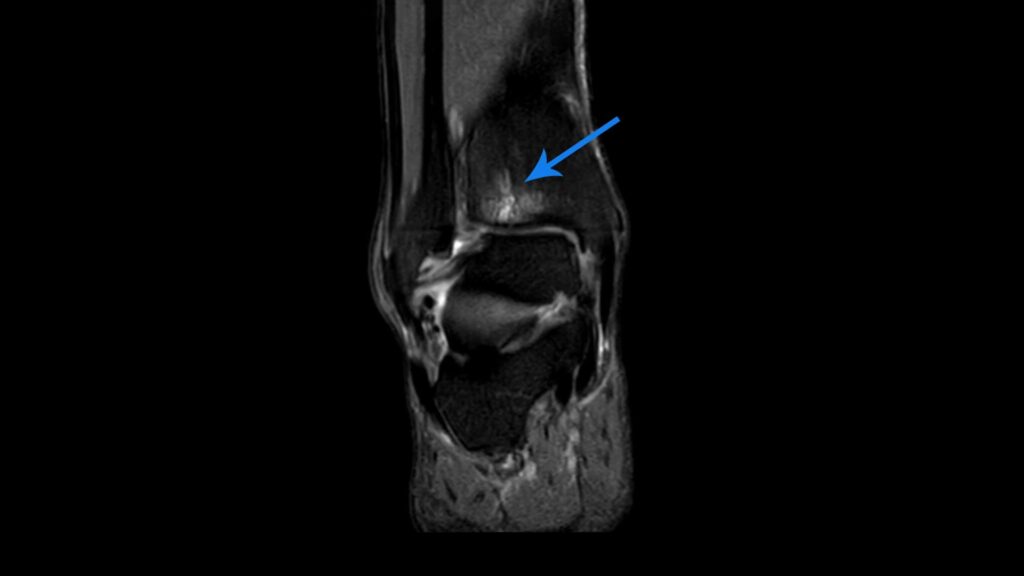

Ein traditionelles Röntgenbild ist für die Erkennung eines Knochenödems meist nicht ausreichend, da diese Art von Verletzung darauf nicht zu erkennen ist. Die sicherste Abklärung erfolgt daher mittels einer MRT (Magnetresonanztomographie), oft in Kombination mit einem zuvor injizierten Kontrastmittel. Dieses lagert sich am Knochenödem ab und macht es so eindeutig erkennbar. Auch neue Techniken wie die Dual-Energie-Computertomographie (DECT) können sehr nützliche Hilfsmittel bei der Erkennung von Knochenödemen sein. Da eine MRT-Untersuchung jedoch aufwendig und teuer ist, sollte sie nur in begründeten Einzelfällen erfolgen, insbesondere wenn der Verdacht auf ein Knochenödem besteht, das nicht von selbst abklingt.

Knochenödem am Knie: Ein häufiger Brennpunkt

Das Kniegelenk, als größtes bewegliches Gelenk des Körpers, ist aufgrund der hohen Belastung, der es ausgesetzt ist, häufiger von einem Knochenödem betroffen als die meisten anderen Körperregionen. Als Knochenödem am Knie bezeichnet man eine Flüssigkeitsansammlung innerhalb des Knochens, die zum Beispiel infolge von Verletzungen oder Knochenerkrankungen auftreten kann.